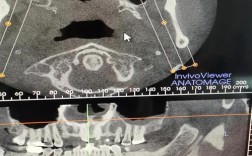

正畸治疗的核心在于精准的诊断与个性化的方案设计,而“北医分析”作为北京大学口腔医院正畸体系中的核心技术方法,凭借其数字化、多维度的评估框架,已成为复杂错颌畸形矫治的重要支撑,北医分析并非单一技术,而是融合了影像学、生物力学、颅颌面生长发育学...